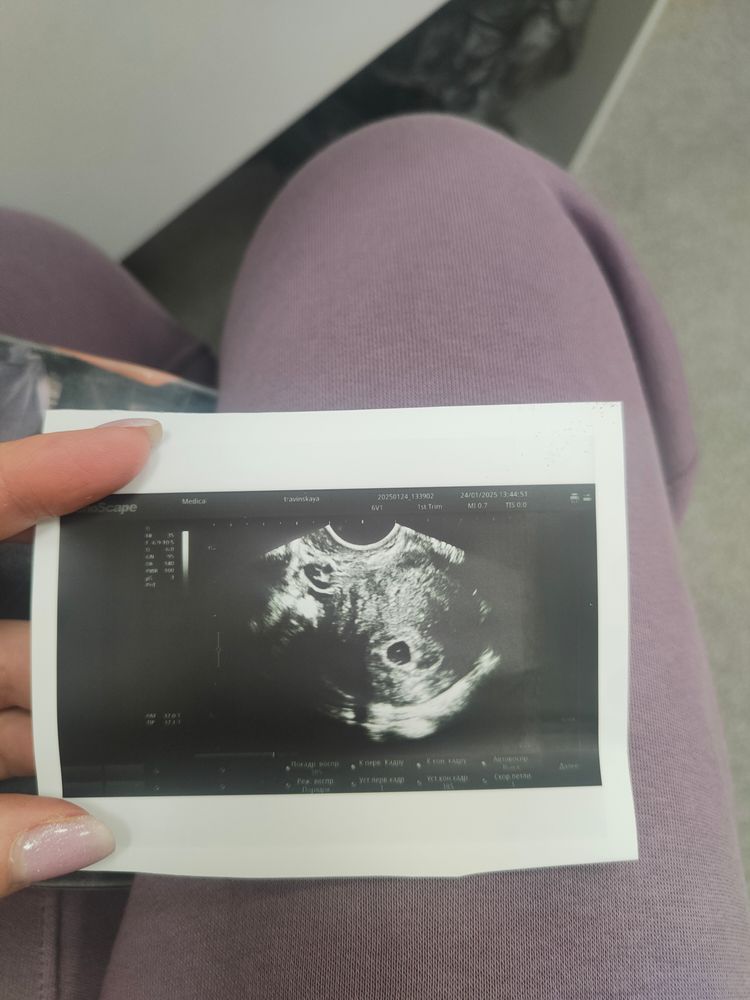

Первое УЗИ срок 5,4 недели

После того как в поликлинике меня отругали, что я пришла слишком рано и ничего не нашли, пытаясь посмотреть через живот, я всё-таки записалась на платное трансвагинальное УЗИ. И все там прекрасно видно! Сдала ещё сегодня ХГЧ, чтоб узнать динамику.

Теперь я могу выдохнуть и тихонько радоваться. Беременность есть и она в матке. И теперь у меня есть снимок, который я вложу в открытку мужу😍 Расскажу ему обо всем в понедельник, когда будем праздновать день нашей свадьбы.

Anita, аппараты в поликлиниках очень плохие. Ну и через живот ещё хуже видно. В платной даже очертания зародыша видны в яйце. И яйцо прям большое 9 мм